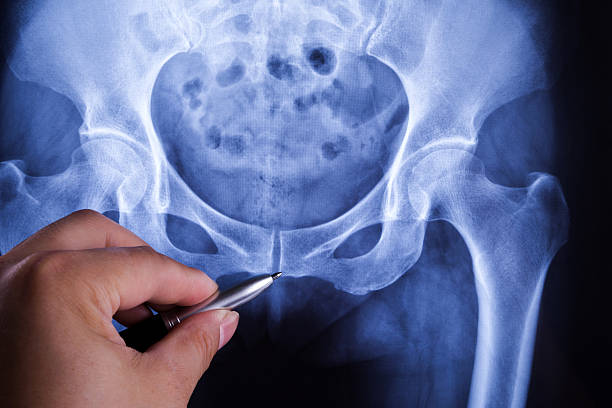

첫째로, 근육과 관절의 문제가 골반통증을 일으킬 수 있습니다. 골반 주변의 근육이 긴장하거나 약해지면 통증이 발생할 수 있습니다. 또한 골반 관절의 이상이나 염증도 골반통증을 유발할 수 있습니다.

근육의 이상은 일상 생활에서의 자세나 운동 방식에 의해 발생할 수 있습니다. 잘못된 자세나 너무 많은 운동으로 인해 근육이 긴장하거나 과도한 부하를 받으면 근육통이 발생하게 됩니다. 또한 근육 부상이나 근육의 약화 역시 골반통증의 원인이 될 수 있습니다.

골반 통증 원인 - 관절

골반 관절의 이상은 골반통증을 일으킬 수 있는 원인 중 하나입니다. 골반 관절의 이상은 관절의 염증이나 변형, 골절 등으로 인해 발생할 수 있습니다. 특히 장시간 동안 한 자세를 유지하거나 골반을 과도하게 사용하는 운동이 해당 관절에 부하를 주어 문제가 생길 수 있습니다.

골반 통증 원인 - 신체적 변화

둘째로, 신체적 요인도 골반통증을 유발할 수 있습니다. 임신이나 출산을 통해 발생한 변화, 체중 증가, 체형의 변화 등이 해당됩니다. 임신 중에는 골반이 넓어지고, 균형을 유지하기 위해 몸이 뒤로 기울거나 앞으로 기울게 됩니다. 이러한 변화로 인해 골반이 과도하게 사용되거나 압력이 가해질 수 있어 골반통증이 발생할 수 있습니다. 또한 체중 증가나 체형 변화로 인해 골반에 부하가 생기면 통증이 발생할 수 있습니다.

신체적 변화는 여러 가지 요인으로 인해 발생할 수 있습니다. 제대로 앉지 않는 자세, 유산소 운동이 부족한 생활, 과체중 등이 해당됩니다. 잘못된 자세로 인해 골반이 불균형하게 사용되거나 압력이 가해져 통증이 발생할 수 있습니다. 또한 유산소 운동이 부족하면 근력이 약화되어 골반 부분에 부하가 생기고 이로 인해 통증이 발생할 수 있습니다.

골반 통증 원인 - 심리적 요인

마지막으로, 심리적인 요인도 골반통증의 원인이 될 수 있습니다. 스트레스, 불안, 우울 등 심리적인 상태가 골반 통증을 유발할 수 있습니다. 심리적인 요인은 신체와 마음이 서로 연결되어 있기 때문에 심리적인 불편함이 신체적인 통증으로 나타날 수 있습니다. 이러한 경우 심리적인 요인을 관리하고 신체적인 치료와 함께 통증을 완화시키는 것이 중요합니다.

골반통증은 다양한 원인으로 인해 발생할 수 있으며, 근육과 관절의 이상, 신체적 요인, 심리적 요인 등이 해당됩니다. 골반통증을 완화시키기 위해서는 원인을 파악하여 적절한 치료와 관리가 필요합니다. 자세한 상담과 전문가의 도움을 받아 원인을 파악하고 적절한 치료 방법을 찾아나가는 것이 중요합니다.